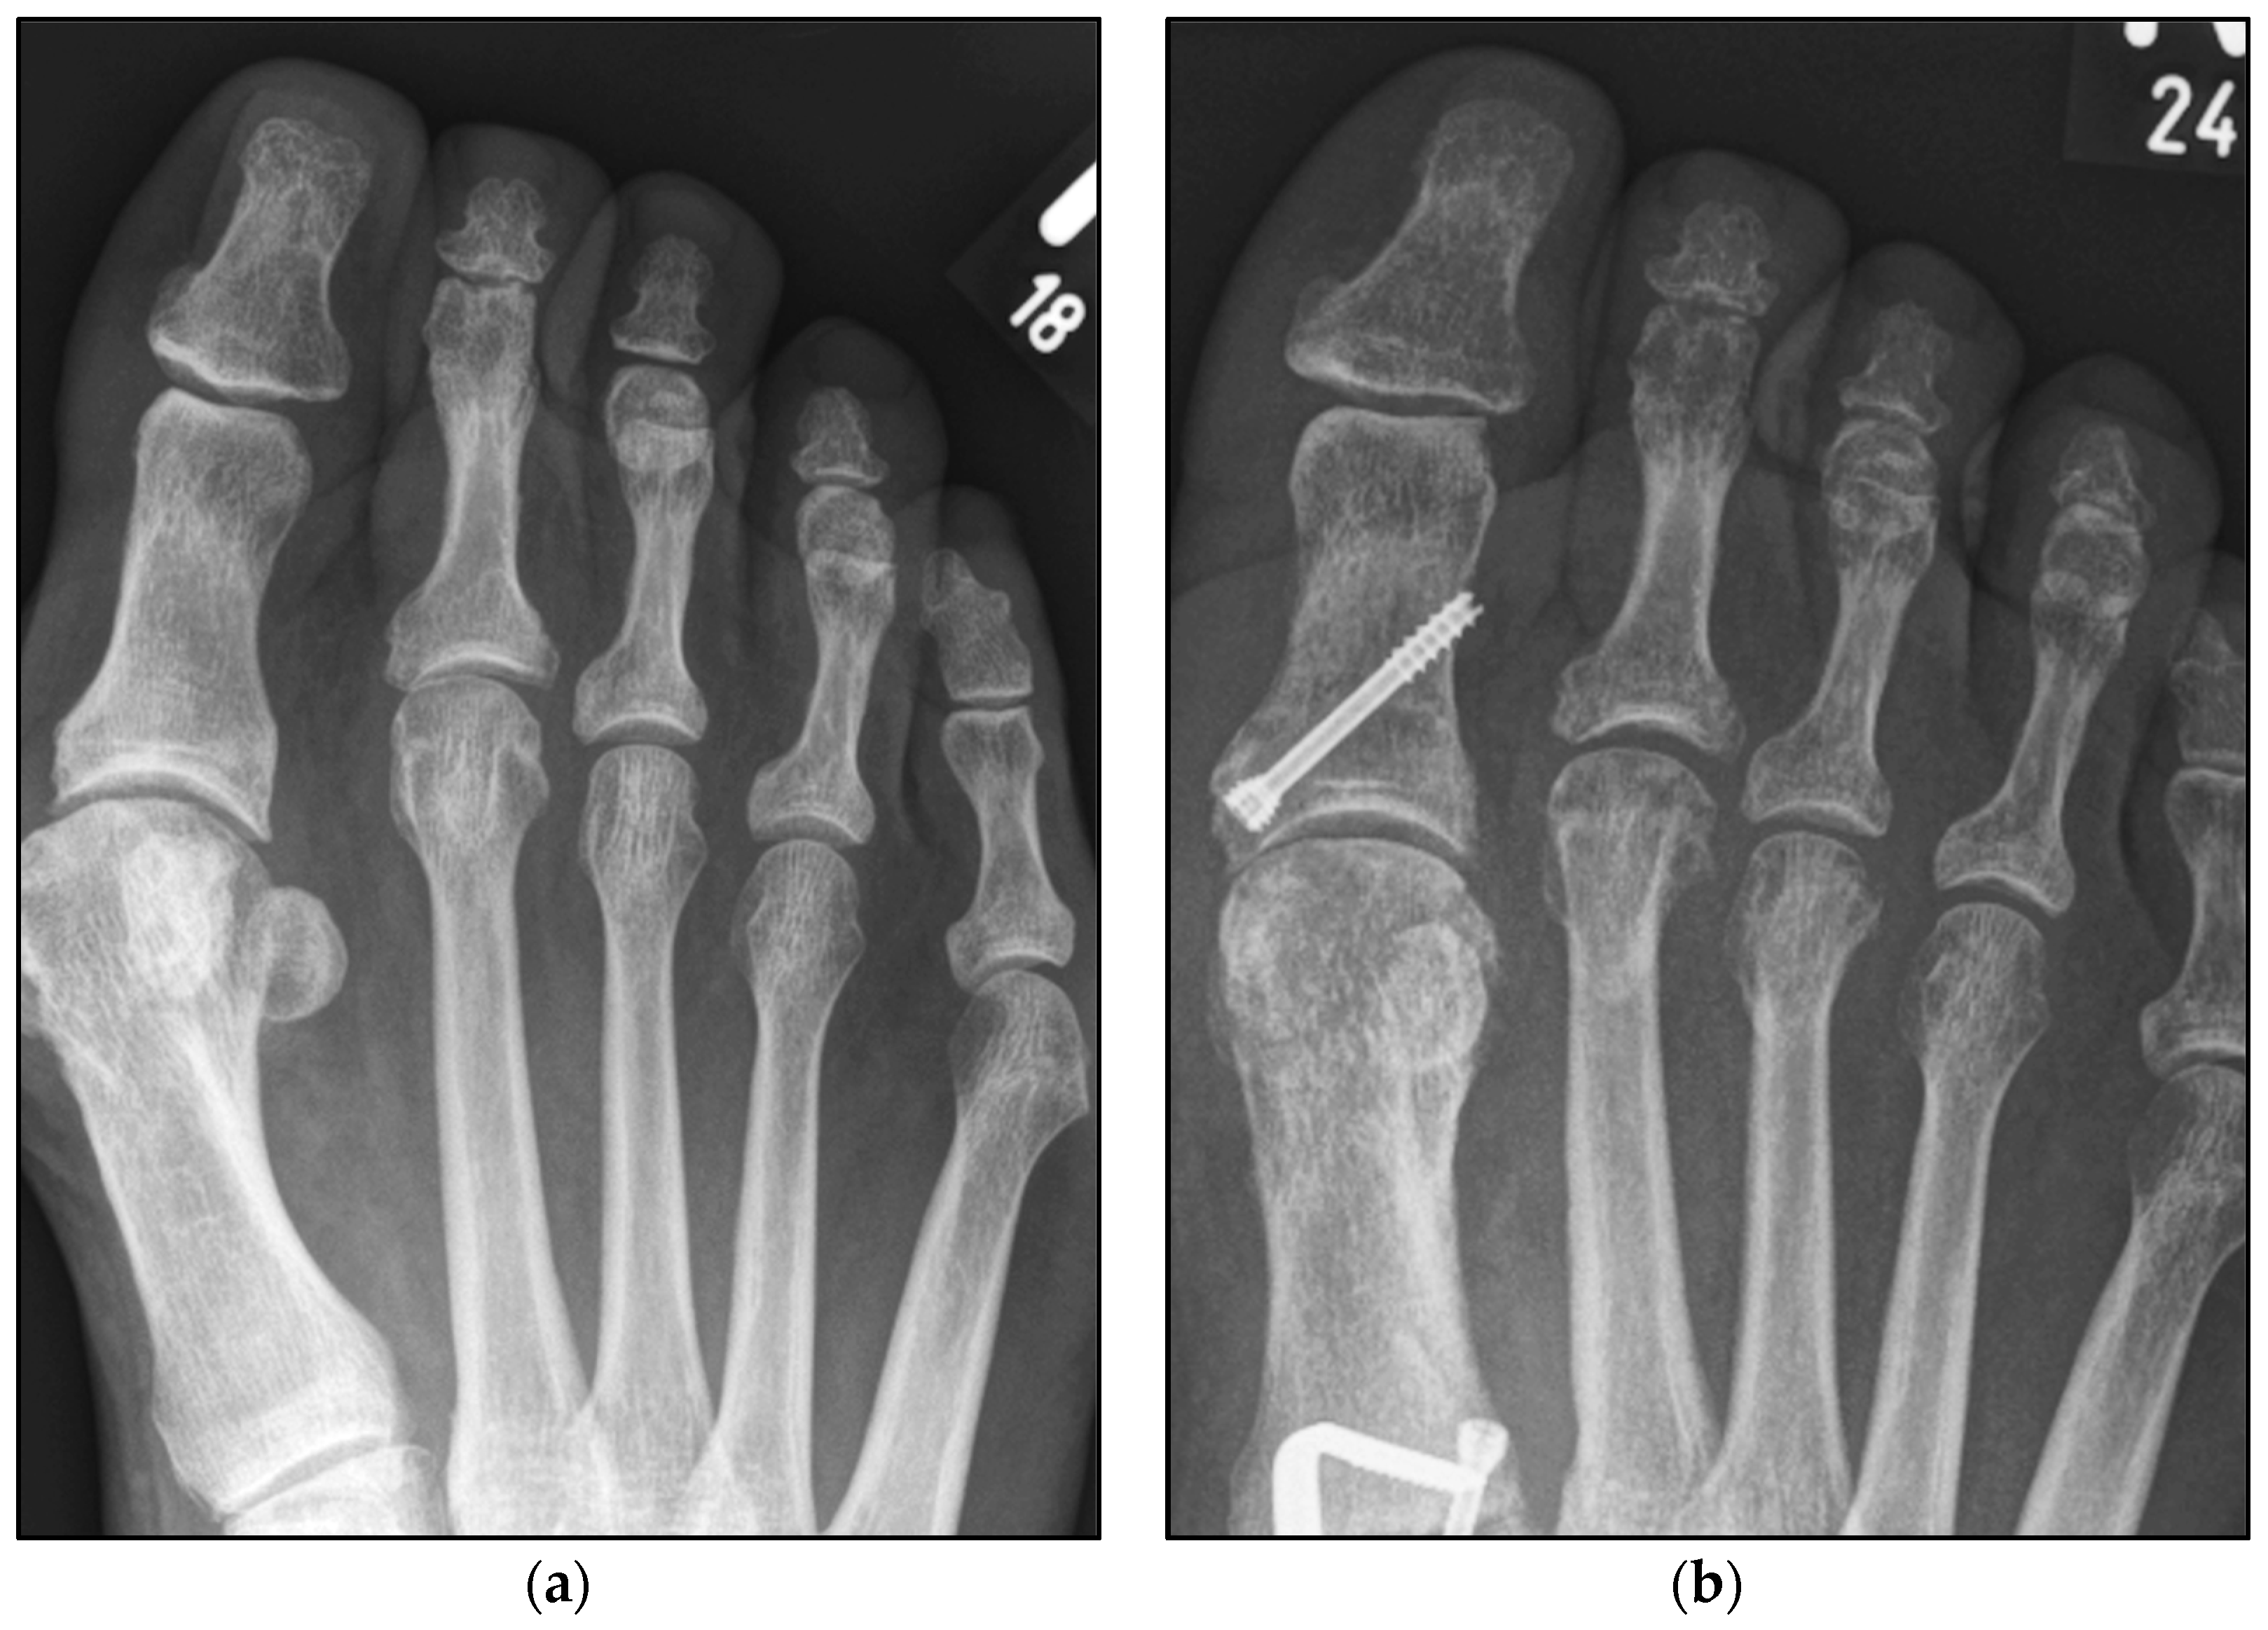

Figure 5.

Pre- and postoperative radiographic results of combined hallux valgus surgery and Weil osteotomy of metatarsal 2 and 3 (group B without screw), right foot. (a) Weight-bearing radiograph: anteroposterior view preoperative, (b) weight-bearing radiograph: anteroposterior view, 3 months postoperative.

We collected the following data from the weight-bearing dorsoplantar foot radiographs after a mean follow-up period of 16 weeks (3.6 months). With no significant difference between groups, the mean MTP angle changed from 9.24° to 12.99° preoperative to postoperative (medial deviation: −n, lateral deviation: +n). As can be seen from the mean SEM in Table 2 and Figure 4 and Figure 5, the maximum medial and lateral deviations from pre- to postoperative were significantly different. The mean MTP only changed from 9.3 to 12.9 and was in the range of a mild lateral deviation. This was also observed equally in both groups (p > 0.05). Of note, the postoperative visibility of the joint space was documented significantly more often in the group without screw fixation; this means the space between the subchondral bone of the metatarsal and the toe was seen without overlay (p < 0.05).

The underlying assumption of our study and the knowledge gained from our results can be further elaborated upon. An inharmonious transverse plane alignment can also be corrected with Weil osteotomy and does not require osteosynthetic fixation of the displaced metatarsal head [24]. The results confirm, based on postoperative weight-bearing radiographs, that the surgically induced correction is maintained regardless of screw fixation. An objectifiable criterion was the metatarsophalangeal angle measured pre- and postoperatively using weight-bearing radiographs in the dorsoplantar view (Figure 1 and Figure 2). In both treatment groups, it was possible to bring the maximum axis deviation closer to the mean value; the mean difference between pre- and postoperative metatarsophalangeal angle was only 3.8°. On average, 10.6 degrees were required to achieve the desired surgical result, regardless of screw fixation (Figure 4 and Figure 5). However, the significantly higher possibility of viewing the affected metatarsal joint space postoperatively can also be considered a successful outcome of the restoration without screw fixation. The visibility of the articular surface, in turn, proves the centering of the metatarsal head in the transverse plane as well as a sufficient correction in the sagittal plane (Figure 6 and Figure 7) [25]. Again, the inability to view the joint space indicates that inadequate correction of the claw toe deformity as well as the metatarsal, which was considered “too long”, was performed [1,14,26].